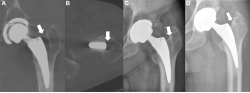

Images in a 65-year-old man with left femoral stem loosening hip implant at surgical revision. Coronal (A) and axial (B) reconstructed 1-mm noncontrast dual-energy CT monoenergetic imaging plus application scans show the presence of a large radiolucency between the lateral aspect of femoral stem and the greater trochanter (arrow). (C, D) On the corresponding anteroposterior radiographs, the periprosthetic radiolucency (arrow) was missed by both readers.